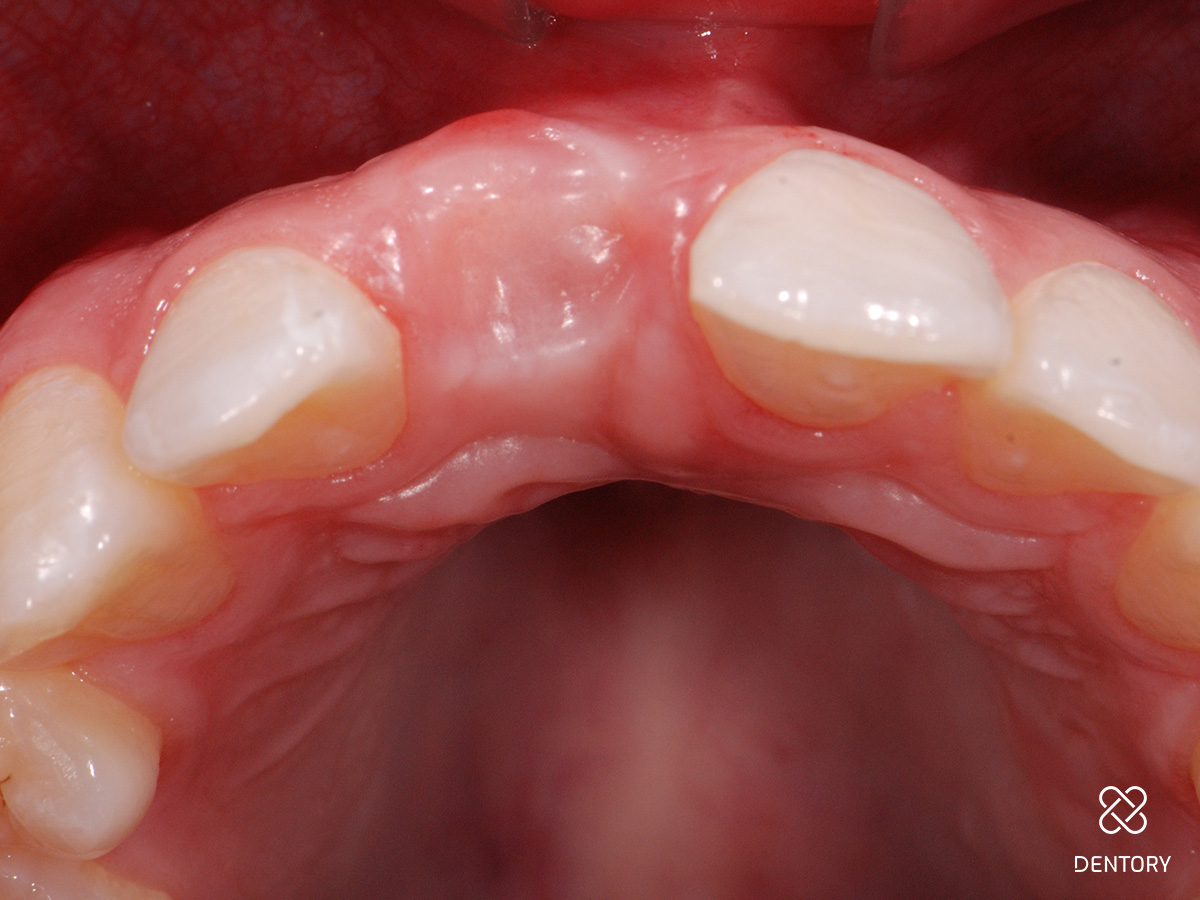

Abbildung 14

Ansicht okklusal.